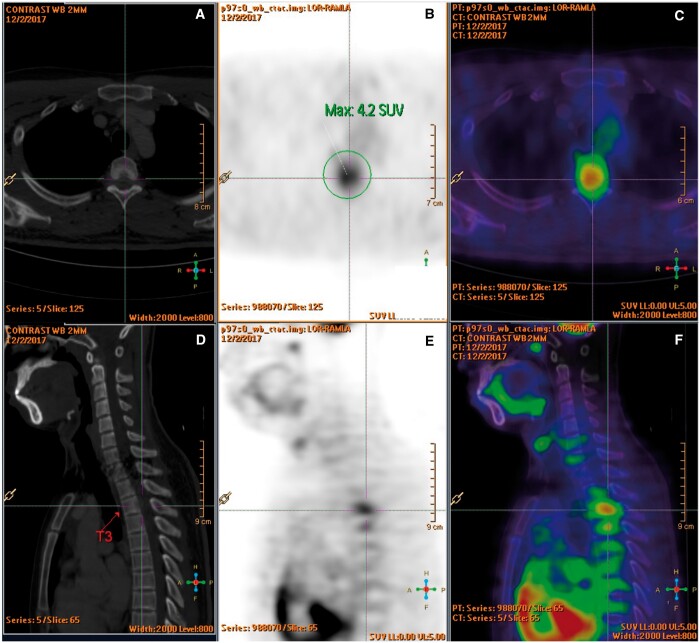

IgG4-related disease is an immune-mediated fibroinflammatory condition. Isolated manifestation in the spine as hypertrophic pachymeningitis is very rare and the mass-like lesion on MRI often mimic tumour or infection. Patients would present with symptoms that result from mass effect or neurovascular compression. Studies showed that serum and CSF IgG4 levels are rarely informative, and therefore, tissue biopsy is crucial for accurate diagnosis. Apart from supporting the diagnosis, MRI is helpful in delineating the extent of disease and follow-up after treatment. A 18F-FDG PET/CT scan is useful in detecting systemic manifestations of IgG4-related disease. Although IgG4-related disease generally responds well to corticosteroid at inflammatory state, relapse is not uncommon. Current treatment strategies for IgG4-related hypertrophic pachymeningitis are high dose corticosteroid therapy and early decompressive surgery to avoid chronic neurological complications. We described a case of a 27-year-old gentleman complaining of lower limb weakness and numbness. MRI showed a mass-like epidural lesion at the thoracic spine causing cord compression. Open biopsy of the epidural mass demonstrated histopathological characteristics of IgG4-related disease. Patient responded well to early surgical decompression of the spinal cord and corticosteroid as evidenced by symptom improvement and resolving mass on subsequent MRI study. However, a follow-up MRI revealed disease recurrence years later.